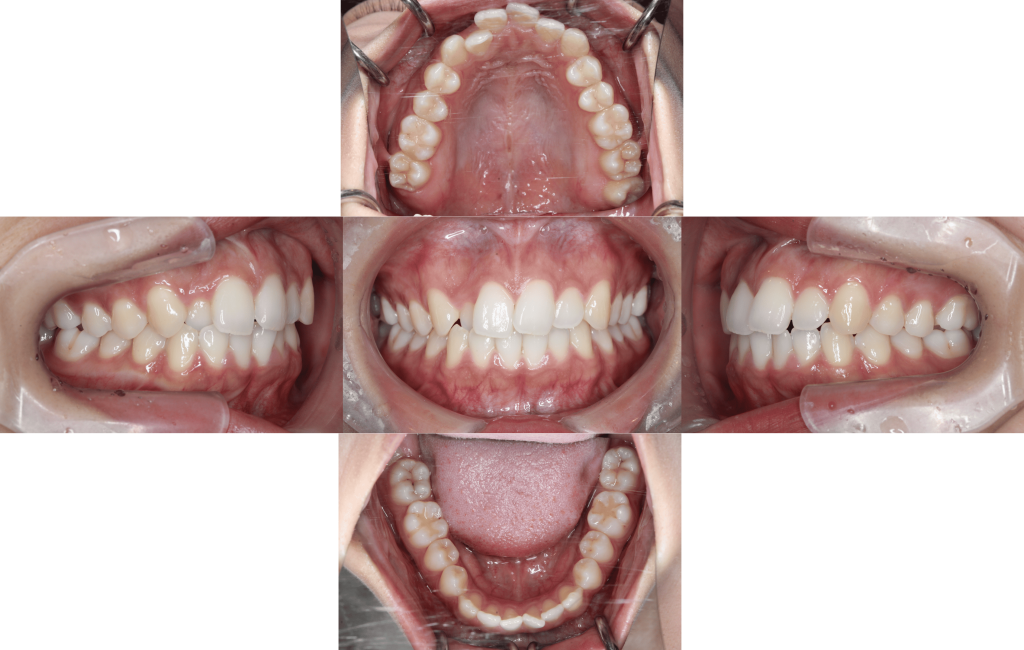

Before

初診